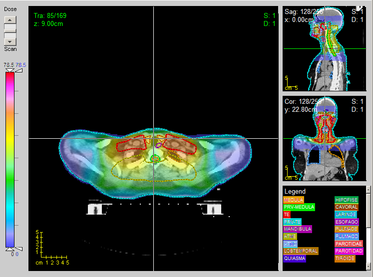

B

eam

A

ngle

O

ptimisation (

BAO

) in

I

ntensity

M

odulated

R

adiation

T

herapy (

IMRT

)